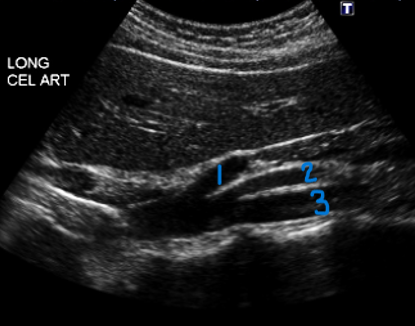

<p>What is #1?</p>

What is #1?

Tunica Adventitia

<p>What is #2?</p>

What is #2?

Tunica Media

<p>What is #3?</p>

What is #3?

Tunica Intima

<p>In this sagittal view, what is #1?</p>

In this sagittal view, what is #1?

Splenic Vein

<p>In this sagittal view, what is #2?</p>

In this sagittal view, what is #2?

Celiac Trunk

<p>In this sagittal view, what is #3?</p>

In this sagittal view, what is #3?

SMA